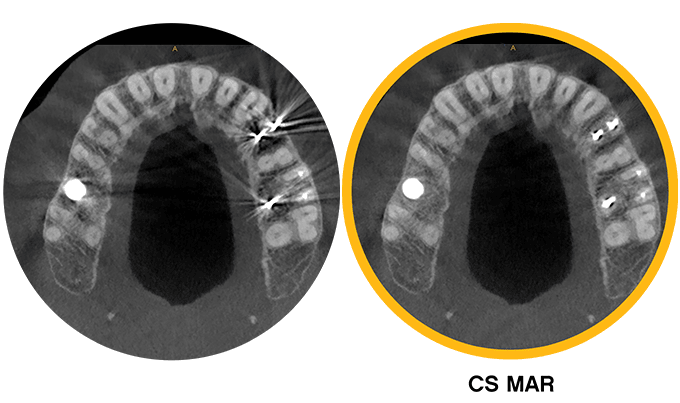

Tecnología exclusiva de reducción de artefactos metálicos (MAR)

Reduce significativamente los artefactos metálicos provocados por restauraciones dentales, implantes y empastes. Además, te permite comparar imágenes de forma dinámica con y sin el filtro, con el objetivo de facilitar la confirmación del diagnóstico del paciente y reducir el riesgo de interpretación errónea.